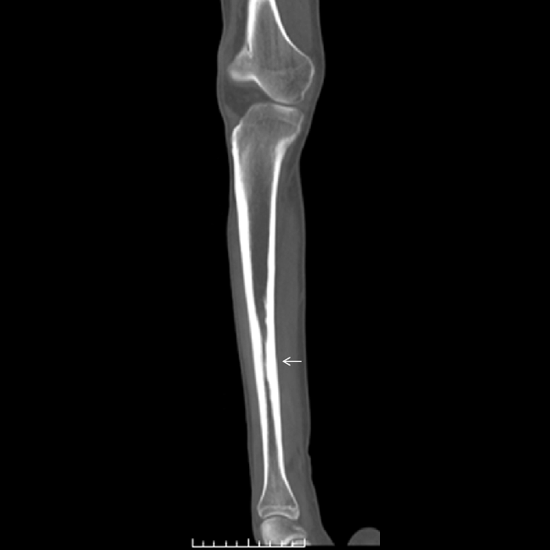

CECT (Contrast Enhanced Computed Tomography) Left Leg is an imaging procedure to view the inner structure of the left leg. In this scan, the thigh bone(femur), tibia and fibula (lower leg bones) and its surrounding soft tissues such as cartilage, ligaments, muscles, blood vessels, as well as tendons, are assessed. The doctor usually recommends this scan for a better and clearer diagnosis of the problems related to leg pain. For this scan, contrast media is injected into the patient and a rotating X-ray beam is used for obtaining the cross-sectional images of the left leg.

• To assess the thigh bone, and lower leg bones for injury and fracture

• To assess the soft tissues such as muscles, ligaments, blood vessels, cartilage, and tendon surrounding to femur, tibia and fibula

• To detect the bone fracture